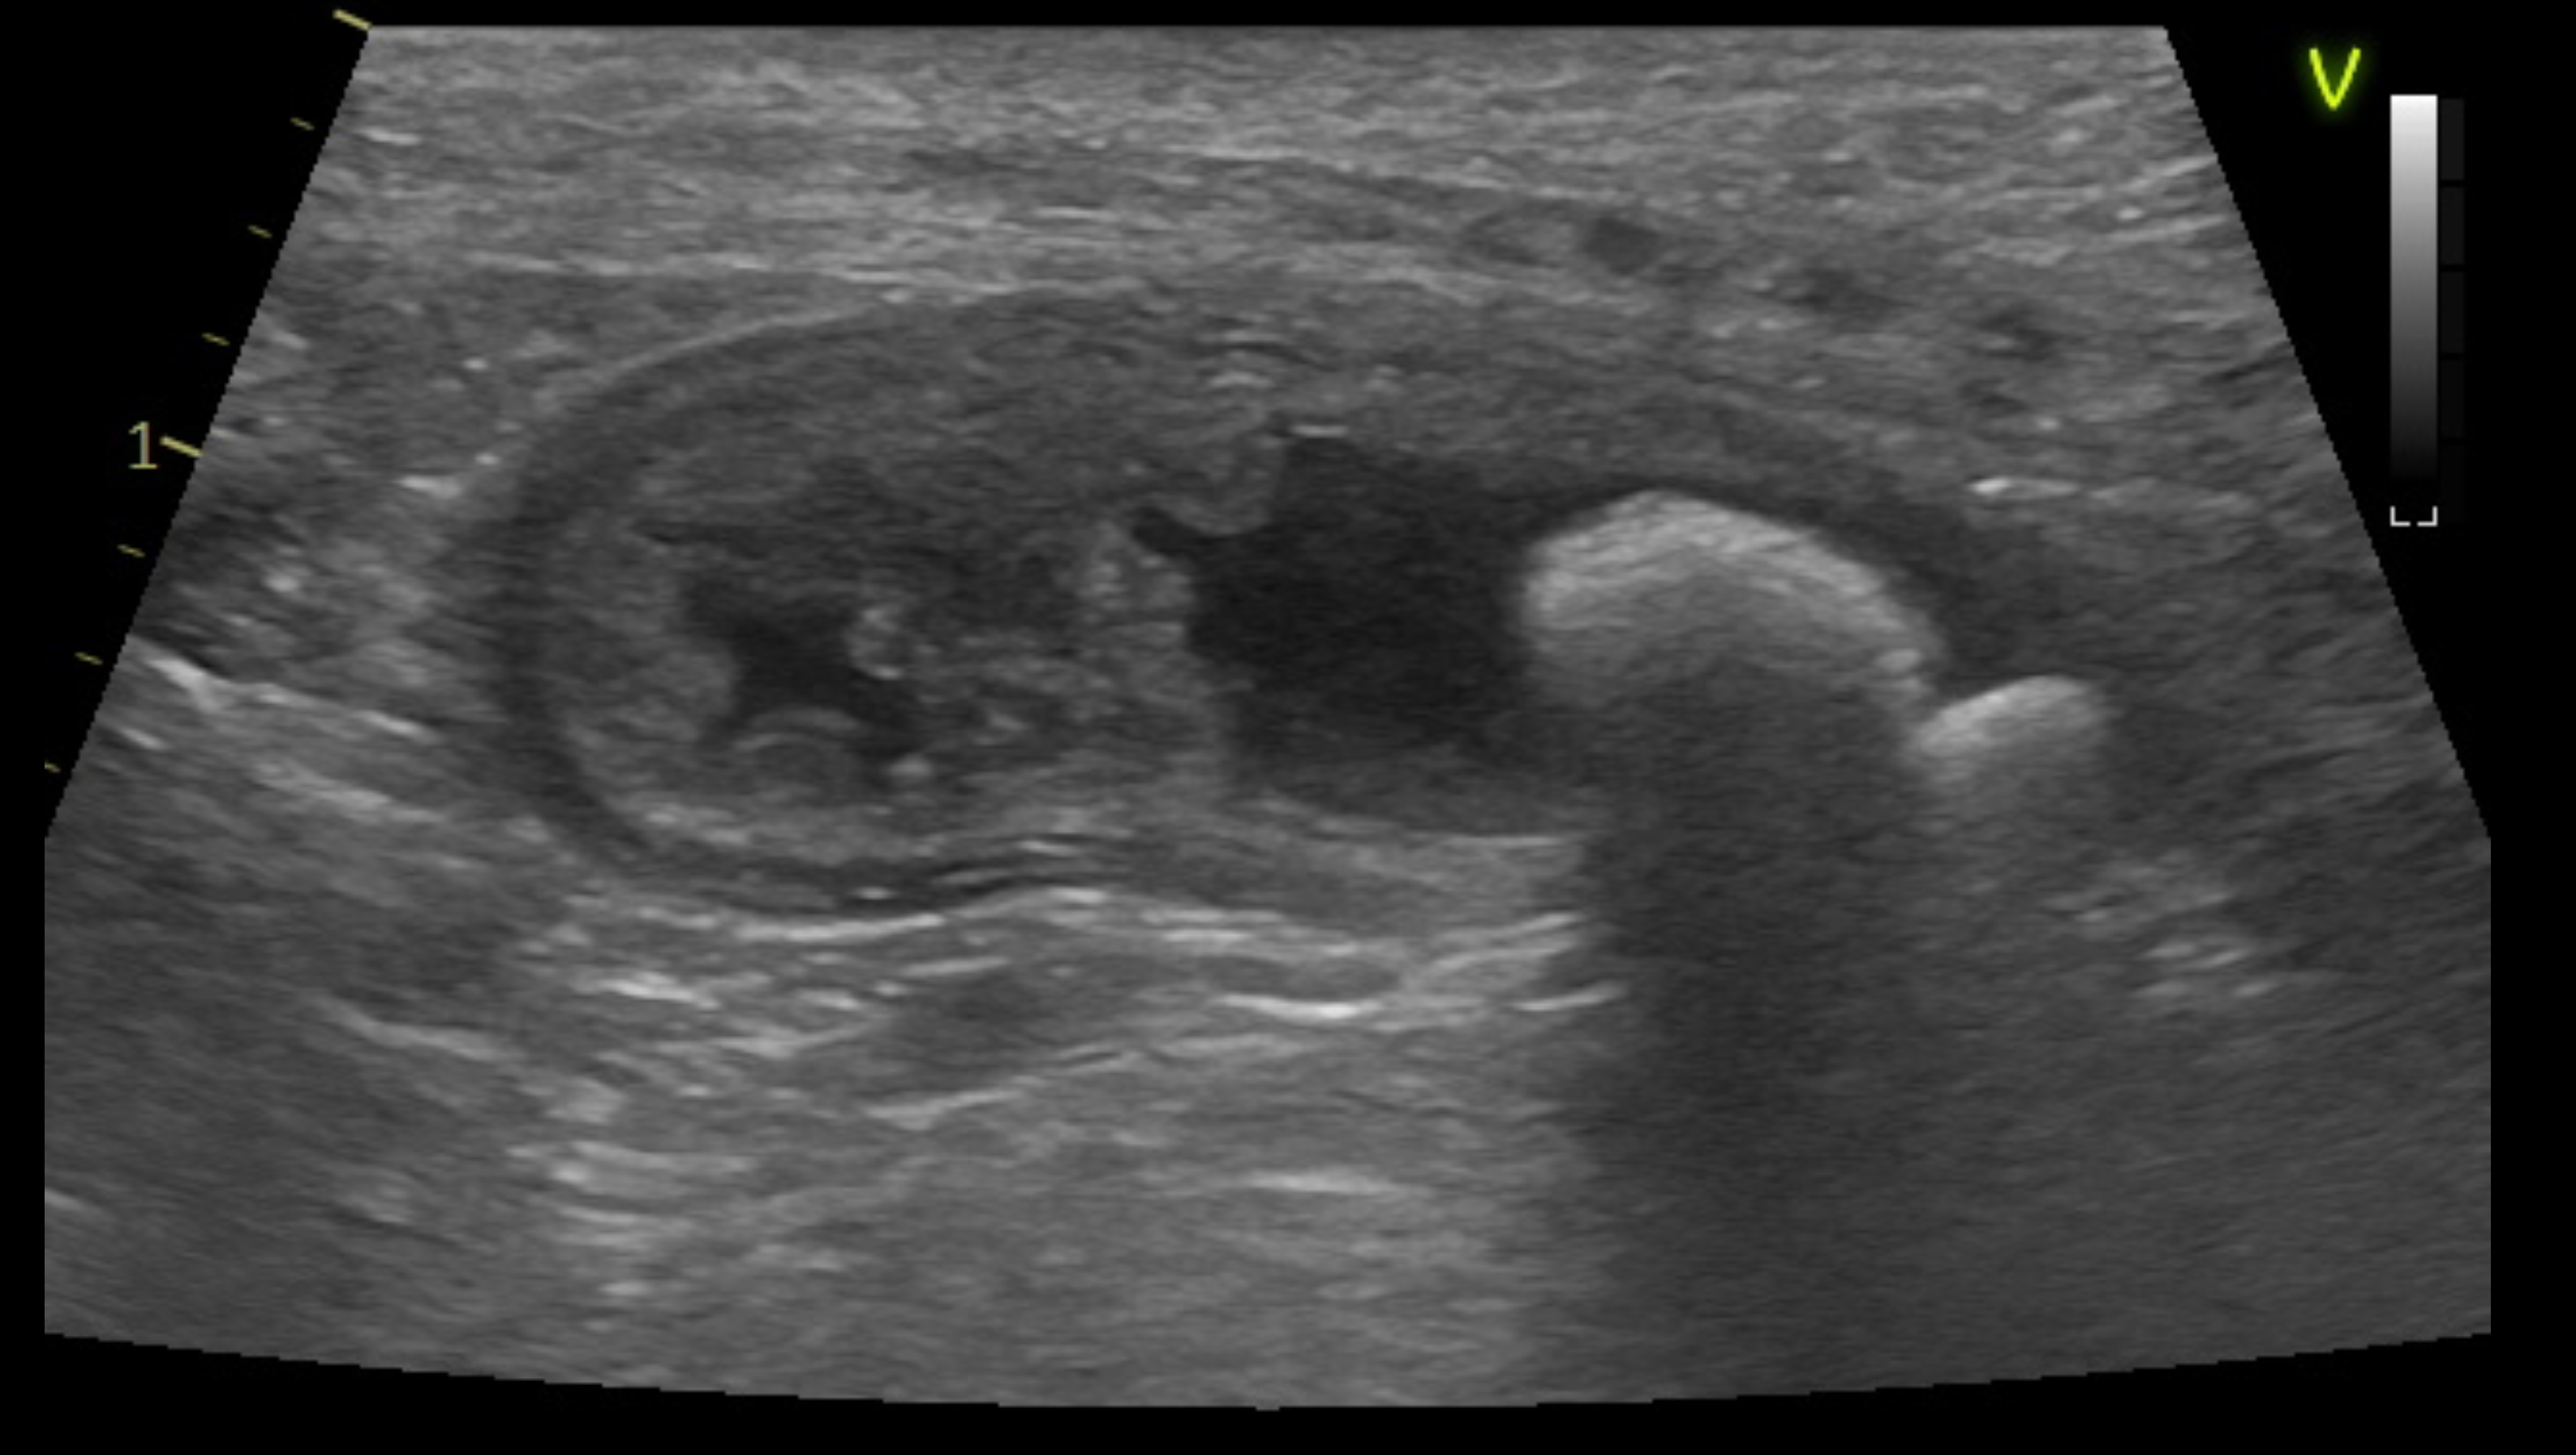

膀胱結石の検査はX線がメインですが、中にはX線に写らない石があるので、超音波と組み合わせて診断をすることになります